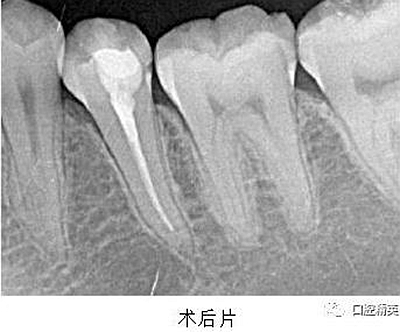

處置:經(jīng)患者及家屬知情同意后,35 局麻,放置橡皮障,去腐,開髓,可見黑色感染物流出,定位根管口,建立直線通路,10# K 銼疏通根管,確定工作長度(19mm),機用鎳鈦器械(M3),次氯酸鈉全程浸泡沖洗,預備根管至 35 號,0.04 錐度,2ml EDTA 沖洗液緩慢勻速沖洗,超聲蕩洗。試主尖 X-ray 可見恰充,吸潮紙尖拭干根管,導AH-Plus 糊劑,連續(xù)波熱牙膠垂直加壓充填,術(shù)后 X-ray可見根管恰充,SDR 封閉根管口,復合樹脂充填窩洞,恢復牙齒形態(tài),調(diào)牙合,拋光。醫(yī)囑

2、扁平根管充填時,應該采用混合技術(shù)。因為主牙膠尖往往不適合扁平根管的形態(tài),使得攜熱器很容易將主牙膠尖全部帶出根管。混合技術(shù)是將連續(xù)波熱牙膠垂直加壓充填法和側(cè)方加壓充填法混合使用,即在插入主尖之后,使用側(cè)方加壓器加壓,追加數(shù)根副尖,直至根尖區(qū)充填致密,繼而使用攜熱器切斷,垂直加壓,熱牙膠回填。

3、根管充填完成之后,要使用流動樹脂或者 SDR 嚴密封閉根管口,酌情墊底,優(yōu)化洞型,之后再行樹脂充填或嵌體等的修復。本例建議行嵌體修復,患者由于個人時間問題,希望暫緩修復,于是采用樹脂充填修復術(shù)。